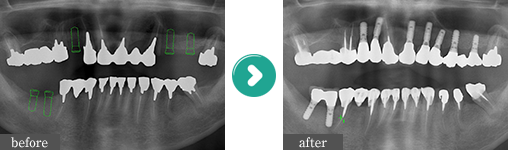

症例